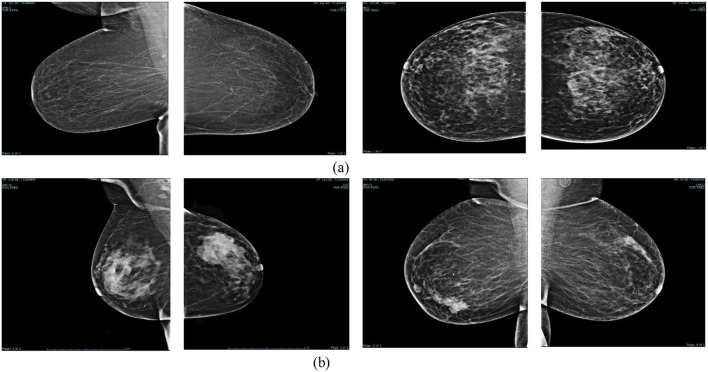

数字化乳房x线摄影对良性和恶性模式的分类是诊断乳腺癌的关键步骤,有助于早期发现并可能挽救许多生命。不同的乳房组织结构往往模糊和隐藏乳房问题。在数字乳房x光检查中对令人担忧的区域(良性和恶性模式)进行分类是放射科医生面临的重大挑战。即使对专家来说,最初的视觉指标也是微妙和不规则的,使识别变得复杂。因此,放射科医生需要一种先进的分类器来帮助识别乳腺癌和对关注区域进行分类。本研究提出了一种使用乳房x线摄影图像进行乳腺癌分类的增强技术。该收集包括来自约旦科技大学阿卜杜拉国王大学医院(KAUH)的真实数据,包括来自5000名18-75岁患者的7205张照片。将图像分类为良性或恶性后,通过重新缩放、归一化和增强进行预处理。采用高升压滤波和对比度限制自适应直方图均衡化(CLAHE)等多融合方法提高图像质量。我们创建了一个独特的残差深度网络(RDN)来提高乳腺癌检测的精度。将建议的RDN模型与MobileNetV2、VGG16、VGG19、ResNet50、InceptionV3、Xception和DenseNet121等著名模型进行了比较。RDN模型的准确率为97.82%,准确率为96.55%,召回率为99.19%,特异性为96.45%,F1评分为97.85%,验证准确率为96.20%。研究结果表明,所提出的RDN模型是一种利用乳房x线摄影图像进行早期诊断的优秀工具,当与多融合和有效的预处理方法相结合时,可以显著提高乳腺癌的检出率。

The categorization of benign and malignant patterns in digital mammography is a critical step in the diagnosis of breast cancer, facilitating early detection and potentially saving many lives. Diverse breast tissue architectures often obscure and conceal breast issues. Classifying worrying regions (benign and malignant patterns) in digital mammograms is a significant challenge for radiologists. Even for specialists, the first visual indicators are nuanced and irregular, complicating identification. Therefore, radiologists want an advanced classifier to assist in identifying breast cancer and categorizing regions of concern. This study presents an enhanced technique for the classification of breast cancer using mammography images. The collection comprises real-world data from King Abdullah University Hospital (KAUH) at Jordan University of Science and Technology, consisting of 7,205 photographs from 5,000 patients aged 18-75. After being classified as benign or malignant, the pictures underwent preprocessing by rescaling, normalization, and augmentation. Multi-fusion approaches, such as high-boost filtering and contrast-limited adaptive histogram equalization (CLAHE), were used to improve picture quality. We created a unique Residual Depth-wise Network (RDN) to enhance the precision of breast cancer detection. The suggested RDN model was compared with many prominent models, including MobileNetV2, VGG16, VGG19, ResNet50, InceptionV3, Xception, and DenseNet121. The RDN model exhibited superior performance, achieving an accuracy of 97.82%, precision of 96.55%, recall of 99.19%, specificity of 96.45%, F1 score of 97.85%, and validation accuracy of 96.20%. The findings indicate that the proposed RDN model is an excellent instrument for early diagnosis using mammography images and significantly improves breast cancer detection when integrated with multi-fusion and efficient preprocessing approaches.